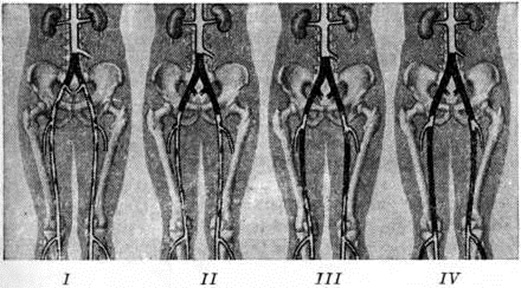

Лериша синдромЛериша синдром (R. Leriche, французский хирург, 1879—1955; синонимы: хроническая закупорка аорты, атеросклеротический тромбоз брюшной аорты, аортоподвздошная окклюзия) — совокупность клинических проявлений, обусловленных хронической окклюзией бифуркации брюшной аорты и подвздошных артерий. Р. Лериш в 1940 год выполнил первую поясничную симпатэктомию и резекцию тромбированной бифуркации брюшной аорты. С 1943 год по предложению Мореля (F. Morel) этот симптомокомплекс стал называться «синдром Лериша». У мужчин заболевание наблюдается в 10 раз чаще. Наиболее часто заболевание отмечается у лиц в возрасте 40—60 лет. Этиология разнообразна. Наблюдаются как врождённые, так и приобретённые окклюзии аортоподвздошного отдела сосудистого русла. К числу врождённых заболеваний относится гипоплазия аорты и фиброзно-мышечная дисплазия подвздошных артерий. Из приобретённых заболеваний наиболее частой причиной является атеросклеротическое поражение (88—94%), неспецифический аортоартериит (5—10%), значительно реже постэмболические тромбозы и другие Патогенез нарушения кровообращения обусловлен степенью и протяжённостью окклюзии аорты и подвздошных артерий, что резко уменьшает объем кровотока в органы таза и нижние конечности. Поэтому на первых этапах заболевания ишемия (смотри полный свод знаний) проявляется во время функциональный нагрузки, а при прогрессировании процесса и в покое. Ведущим проявлением заболевания является снижение перфузионного давления в дистальном сосудистом русле и нарушение микроциркуляции (смотри полный свод знаний), а затем и обменных процессов в тканях. В характере компенсации нарушений гемодинамики большое значение имеет развитие коллатерального кровообращения. Патологическая анатомия зависит от этиологии поражения. Обнаруживаются характерные для атеросклероза изменения аорты (смотри полный свод знаний Атеросклероз). Максимальные изменения наблюдаются в области бифуркации аорты и в месте отхождения внутренней подвздошной артерии. Часто имеется выраженный кальциноз стенки аорты и артерии (смотри полный свод знаний Кальциноз), во многих случаях — пристеночный тромбоз (смотри полный свод знаний). Гистологический картина атеросклеротического поражения не имеет особенностей. При неспецифическом аортоартериите в первую очередь поражается также аорта. Для этого заболевания характерен выраженный перипроцесс, резкое утолщение стенки аорты за счёт воспаления наружной, средней и реактивного утолщения внутренней оболочки. Нередко отмечается кальциноз стенки. Клиническая картина зависит от протяжённости поражения сосудистого русла и степени развития коллатерального кровообращения. В зависимости от проксимального уровня окклюзии брюшной аорты выделяют 3 варианта Лериша синдром (рисунок 1): низкая окклюзия (А) — дистальнее нижней брыжеечной артерии; средняя окклюзия (Б) — проксимальнее нижней брыжеечной артерии и высокая окклюзия (В) — сразу дистальнее или на уровне почечных артерий. В зависимости от поражения дистального сосудистого русла целесообразно выделять 4 типа (рисунок 2): I тип — поражение аорты и общих подвздошных артерий; тип — поражение аорты, общих и наружных подвздошных артерий; тип — к изменениям при II типе присоединяется поражение поверхностной бедренной артерии; IV тип— дополнительно поражены сосуды голени. При всех типах поражения дистального сосудистого русла выделяется вариант «а» — с проходимой глубокой артерией бедра и вариант «б» — имеется стеноз или окклюзия устья этой артерии. Следует отметить, что при этом имеется в виду не только окклюзия (полная облитерация) сосуда, но и резкие стенозы (более 75% диаметра). Поражение дистального сосудистого русла у одного и того же больного может быть асимметричным. Различают 4 степени ишемии: I — начальные проявления; IIA — появление перемежающейся хромоты через 300—500 метров ходьбы; II Б — появление перемежающейся хромоты через 200 метров ходьбы; III — боли через 25— 50 метров ходьбы или в покое; IV — наличие язвенно-некротических изменений. Первым симптомом заболевания обычно являются боли, которые появляются в икроножных мышцах при ходьбе. Практически 90% больных с Лериша синдром обращаются к врачу по поводу перемежающейся хромоты (смотри полный свод знаний). |